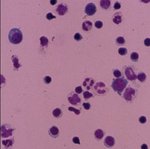

Für die Labordiagnostik ist immer eine parallele Einsendung von Liquor und Serum erforderlich. Die Untersuchung besteht zunächst aus dem Grundprogramm: Zellzahl, Gesamteiweiß (nur Liquor), IgG-, IgA- und IgM-Quotientendiagramm (Reiberschema), und dem Nachweis einer intrathekalen Antikörpersynthese. Hierfür werden Oligoklonale IgG, Borrelien-IgG- und IgM-Antikörperindex in Serum und Liquor bestimmt. Durch die gleichzeitige Immunoblotuntersuchung bei grenzwertigem und positivem Antikörpernachweis können die Nachweisempfindlichkeit und die Spezifität des Systems noch gesteigert werden.

Nur selten positiv bei der Neuroborreliose ist der molekularbiologische Nachweis der Borrelien-DNA im Liquor mit der PCR-Methode. Ein negatives PCR-Ergebnis kann deshalb eine aktive Infektion nicht ausschließen.